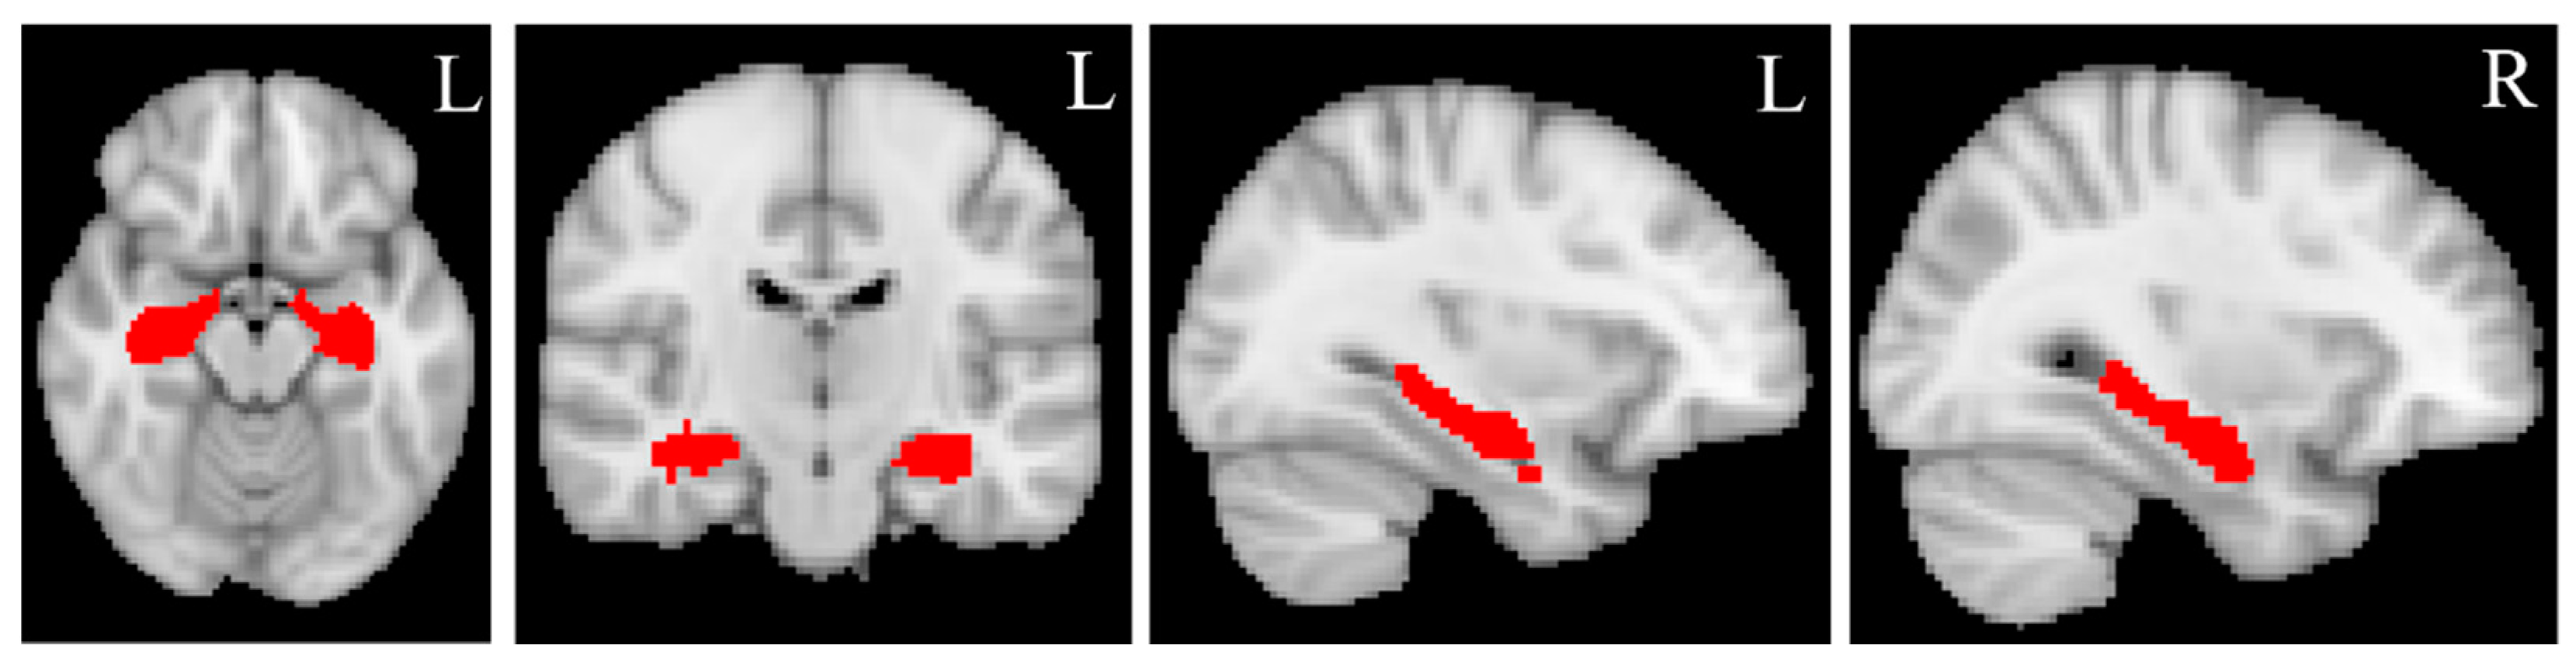

The binary masks of the bilateral hippocampus (Figure 2) were created from the automated anatomical labelling (AAL) atlas (https://www.gin.cnrs.fr/en/tools/aal/, accessed on 20 June 2022) [38], version 1, in the MNI space using “fslmath”, a function of FSL. MD and MK values for the bilateral hippocampus were extracted from the MD and MK maps in the standard space using the function “fslmeants” in FSL for each participant. Figure 3 displays the whole processing steps of DKI.

Figure 2.

Hippocampal masks. The bilateral hippocampal masks are created from Automated anatomical labeling (AAL) atlas, version 1, in standard MNI space using “fslmaths”, a function implemented in FSL. L = left, R = right. The red color represents the bilateral hippocampal masks.